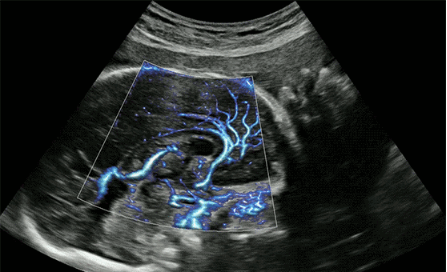

CrystalLive?是三星最新的超聲成像引擎,同時(shí)增強(qiáng)了2D圖像處理能力、3D渲染能力和彩色信號處理能力,能夠在復(fù)雜情況下提供出色的圖像性能,具備檢測外周血管、微循環(huán)血流的能力。

3D/4D成像方面,Hera i 10通過結(jié)合先進(jìn)的圖像渲染技術(shù),著重加強(qiáng)了邊緣和小結(jié)構(gòu)的可視化能力。